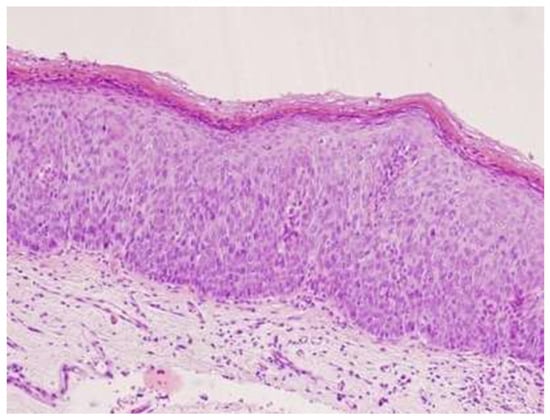

- Darragh, T.M.; Colgan, T.J.; Cox, J.T.; Heller, D.S.; Henry, M.R.; Luff, R.D.; McCalmont, T.; Nayar, R.; Palefsky, J.M.; Stoler, M.H.; et al. The Lower Anogenital Squamous Terminology Standardization Project for HPV-Associated Lesions. Int. J. Gynecol. Pathol. 2013, 32, 76–115. [Google Scholar] [CrossRef]